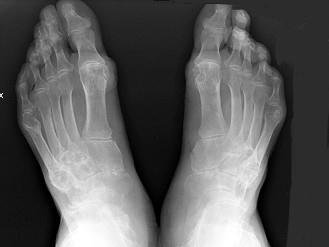

问题 男,72岁,手足小关节红肿热痛,白细胞升高,血沉快,血尿酸升高,结合图像,最可能诊断是?(?)

选项 A.类风湿关节炎 B.退行性骨关节病 C.痛风性关节炎 D.假痛风 E.滑膜炎

答案 C